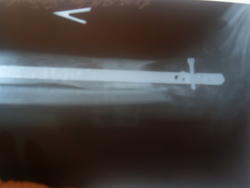

Хирургическое лечение: (июнь 2010) резекция таранной кости, так как она была сильно разрушена фиброзной тканью, удалили эндопротез пяточной кости. Сделали остеотомию левой большеберцовой кости на уровне с/3. Монтаж аппарата внешней фиксации на голень и стопу. С целью удлинения голени для замещения таранной и пяточной кости. Через 5 месяцев была выполнена операция демонтаж аппарата Илизарова, интрамедуллярный остеосинтез с блокированием левой большеберцовой кости, открытая адаптация стопы и фиксация винтами и спицами к большеберцовой кости. (г.Санкт-Петербург, Россия)